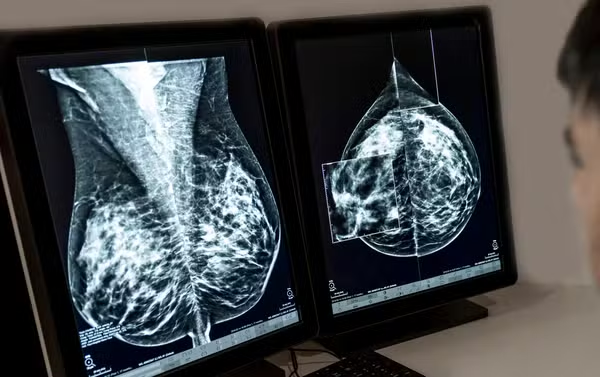

Pesquisadores chineses descobriram um mecanismo que ajuda células de câncer de mama a escapar da ação do nosso sistema imune.

O estudo mostra que esses tumores conseguem alterar um processo natural de defesa do organismo, o que favorece o avanço da doença.